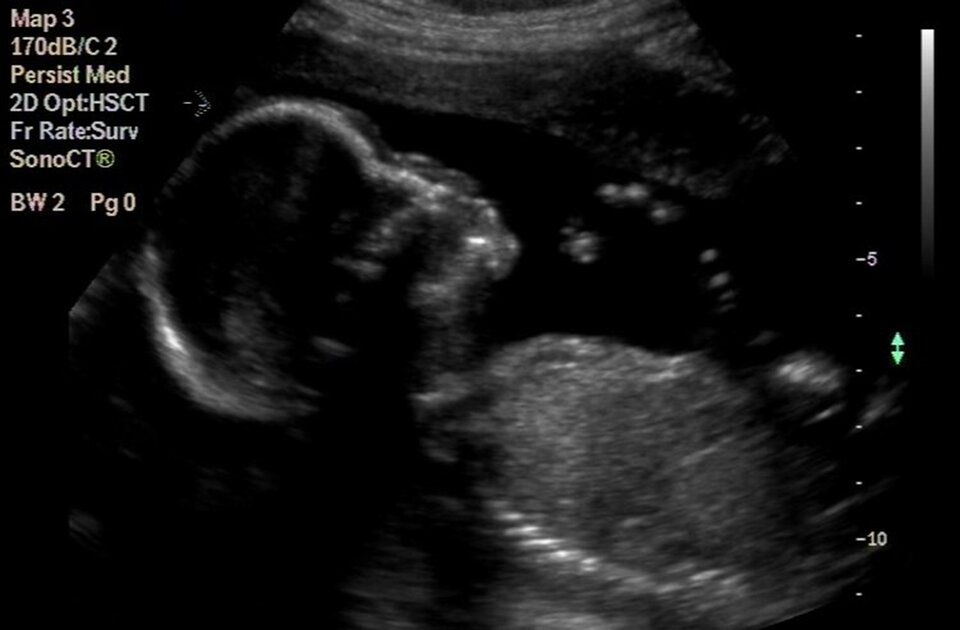

II trymestr | 3 miesiąc | 6 cm | Jelita przesuwają się z pępowiny do brzucha płodu, pracują nerki. Płód rusza rękami i ustami. Na podstawie badania USG można określić płeć płodu oraz sprawdzić, czy jego rozwój jest prawidłowy (np. wykluczyć występowanie wad genetycznych). Do erytropoezy włącza się śledziona. |

Do oceny stanu płodu, jego prawidłowego rozwoju i wykrycia wad rozwojowych służą badania prenatalne (diagnostyka prenatalna), przeprowadzane w pierwszym trymestrze.

Metody nieinwazyjne nie ingerują bezpośrednio w środowisko płodu, a zatem nie wiążą się z ryzykiem powikłań w przebiegu ciąży. Stosuje się je u wszystkich kobiet ciężarnych, niezależnie od wieku. Należą do nich: badanie USG, oraz testy biochemiczne i badania genetyczne z krwi matczynej.